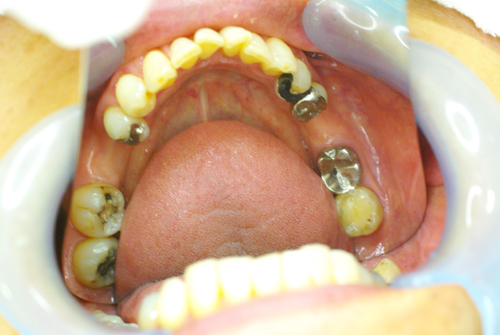

術前の口腔内写真です

下の奥歯が左右あわせて2本ありません。歯がない所にインプラントを埋入します。